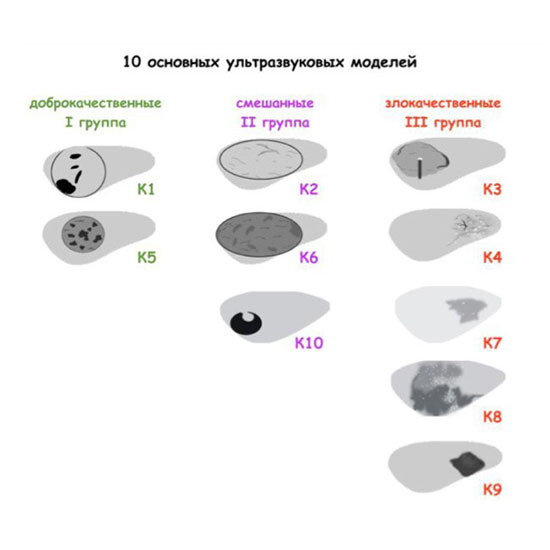

Исследование щитовидной железы одно из самых простых в ультразвуковой диагностике. Подходов к диагностике очень много, и когда они друг другу противоречат необходимо обратиться к международной практике. На сегодняшний день наиболее авторитетное международная организация это American Institute of Ultrasound in Medicine (AIUM). Данной организацией, по вопросам щитовидной железы, утверждены две системы это ACR (American College of Radiology) Ti-RADS и авторская система (С.И. Матящук) ThyrNoDUM.

Суть в том, что достоверно по сонограмме не возможно определить гистологический тип узлового образования, однако мы может определить статистический тип (ThyrNoDUM) и класс риска с показанием к биопсии по скоринговой системе (ACRTi-RADS).

Рассмотрим системы на примерах:

1) Узел занимает всю левую долю, но прорастает капсулу щитовидной железы (0 баллов), больше широкий чем высокий (0 баллов), не имеет кальцинатов (0 баллов), с ровным четким контуром (0 баллов), изоэхогенный (1 балл), тканевой структуры (2 балла). Количество баллов 3, ACRTi-RADS 3, ThyrNoDUMК3. Показана пункция в связи с большим диаметром узла (более 2,5см для Ti-RADS 3)

2) Узел у перешейка, не прорастает капсулу щитовидной железы (0 баллов), больше широкий чем высокий (0 баллов), не имеет кальцинатов (0 баллов), с ровным четким контуром (0 баллов), гипоэхогенный (2 балла), тканевой структуры (2 балла). Количество баллов 4, ACRTi-RADS4, ThyrNoDUMК6. Пункция не показана в связи с малым диаметром узла (более 1,5 см для Ti-RADS4), рекомендовано наблюдение.

3) Узел правой доли, не прорастает капсулу щитовидной железы (0 баллов), больше широкий чем высокий (0 баллов), не имеет кальцинатов (0 баллов), с ровным четким контуром (0 баллов), изоэхогенный (1 балл), смешанной структуры (1 балл). Количество баллов 2, ACRTi-RADS2, ThyrNoDUMК1. Пункция не показана в связи с низким риском.

4) Узел правой доли, не прорастает капсулу щитовидной железы (0 баллов), больше широкий чем высокий (0 баллов), не имеет кальцинатов (0 баллов), с ровным четким контуром (0 баллов), изоэхогенный (1 балл), смешанной структуры (кистозно солидный) (1 балл). Количество баллов 2, ACRTi-RADS2, ThyrNoDUMК1. Пункция не показана в связи с низким риском.